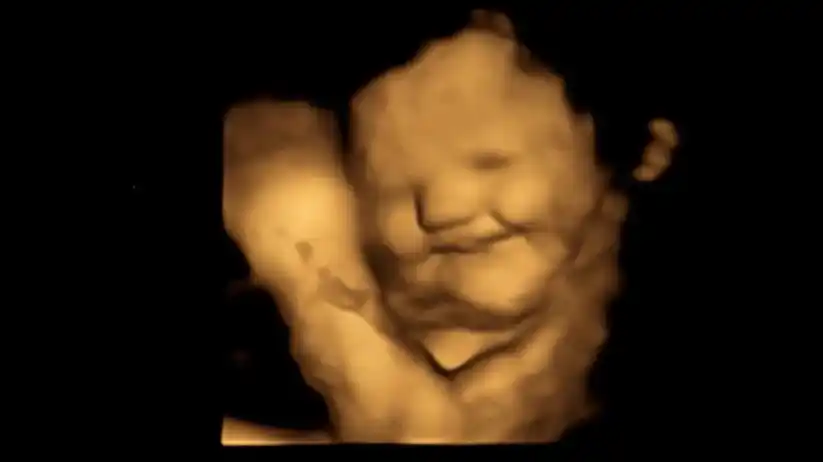

Los fetos crean más “cara de risa” en el útero cuando se exponen al sabor de las zanahorias que consume su madre y crean más “cara de llanto” cuando se exponen al kale, también conocido como col rizada, según un estudio publicado este miércoles en la revista académica Psychological Science.

Mientras que el sabor de la zanahoria puede ser descrito como “dulce” por los adultos, se eligió el kale porque transmite más amargor a los bebés que otras verduras verdes como las espinacas, el brócoli o los espárragos, según el estudio. Tras un período de espera de 20 minutos después del consumo, las mujeres se sometieron a ecografías en 4D, que se compararon con imágenes en 2D de los fetos.

Los tirones de las comisuras de los labios, que sugieren una sonrisa o una risa, fueron significativamente mayores en el grupo de la zanahoria en comparación con el grupo del kale y el grupo de control. Mientras que movimientos como la elevación del labio superior, la caída del labio inferior, la presión de los labios y una combinación de ellos, que sugieren una cara de molestia o llanto, fueron mucho más comunes en el grupo del kale que en los otros grupos.